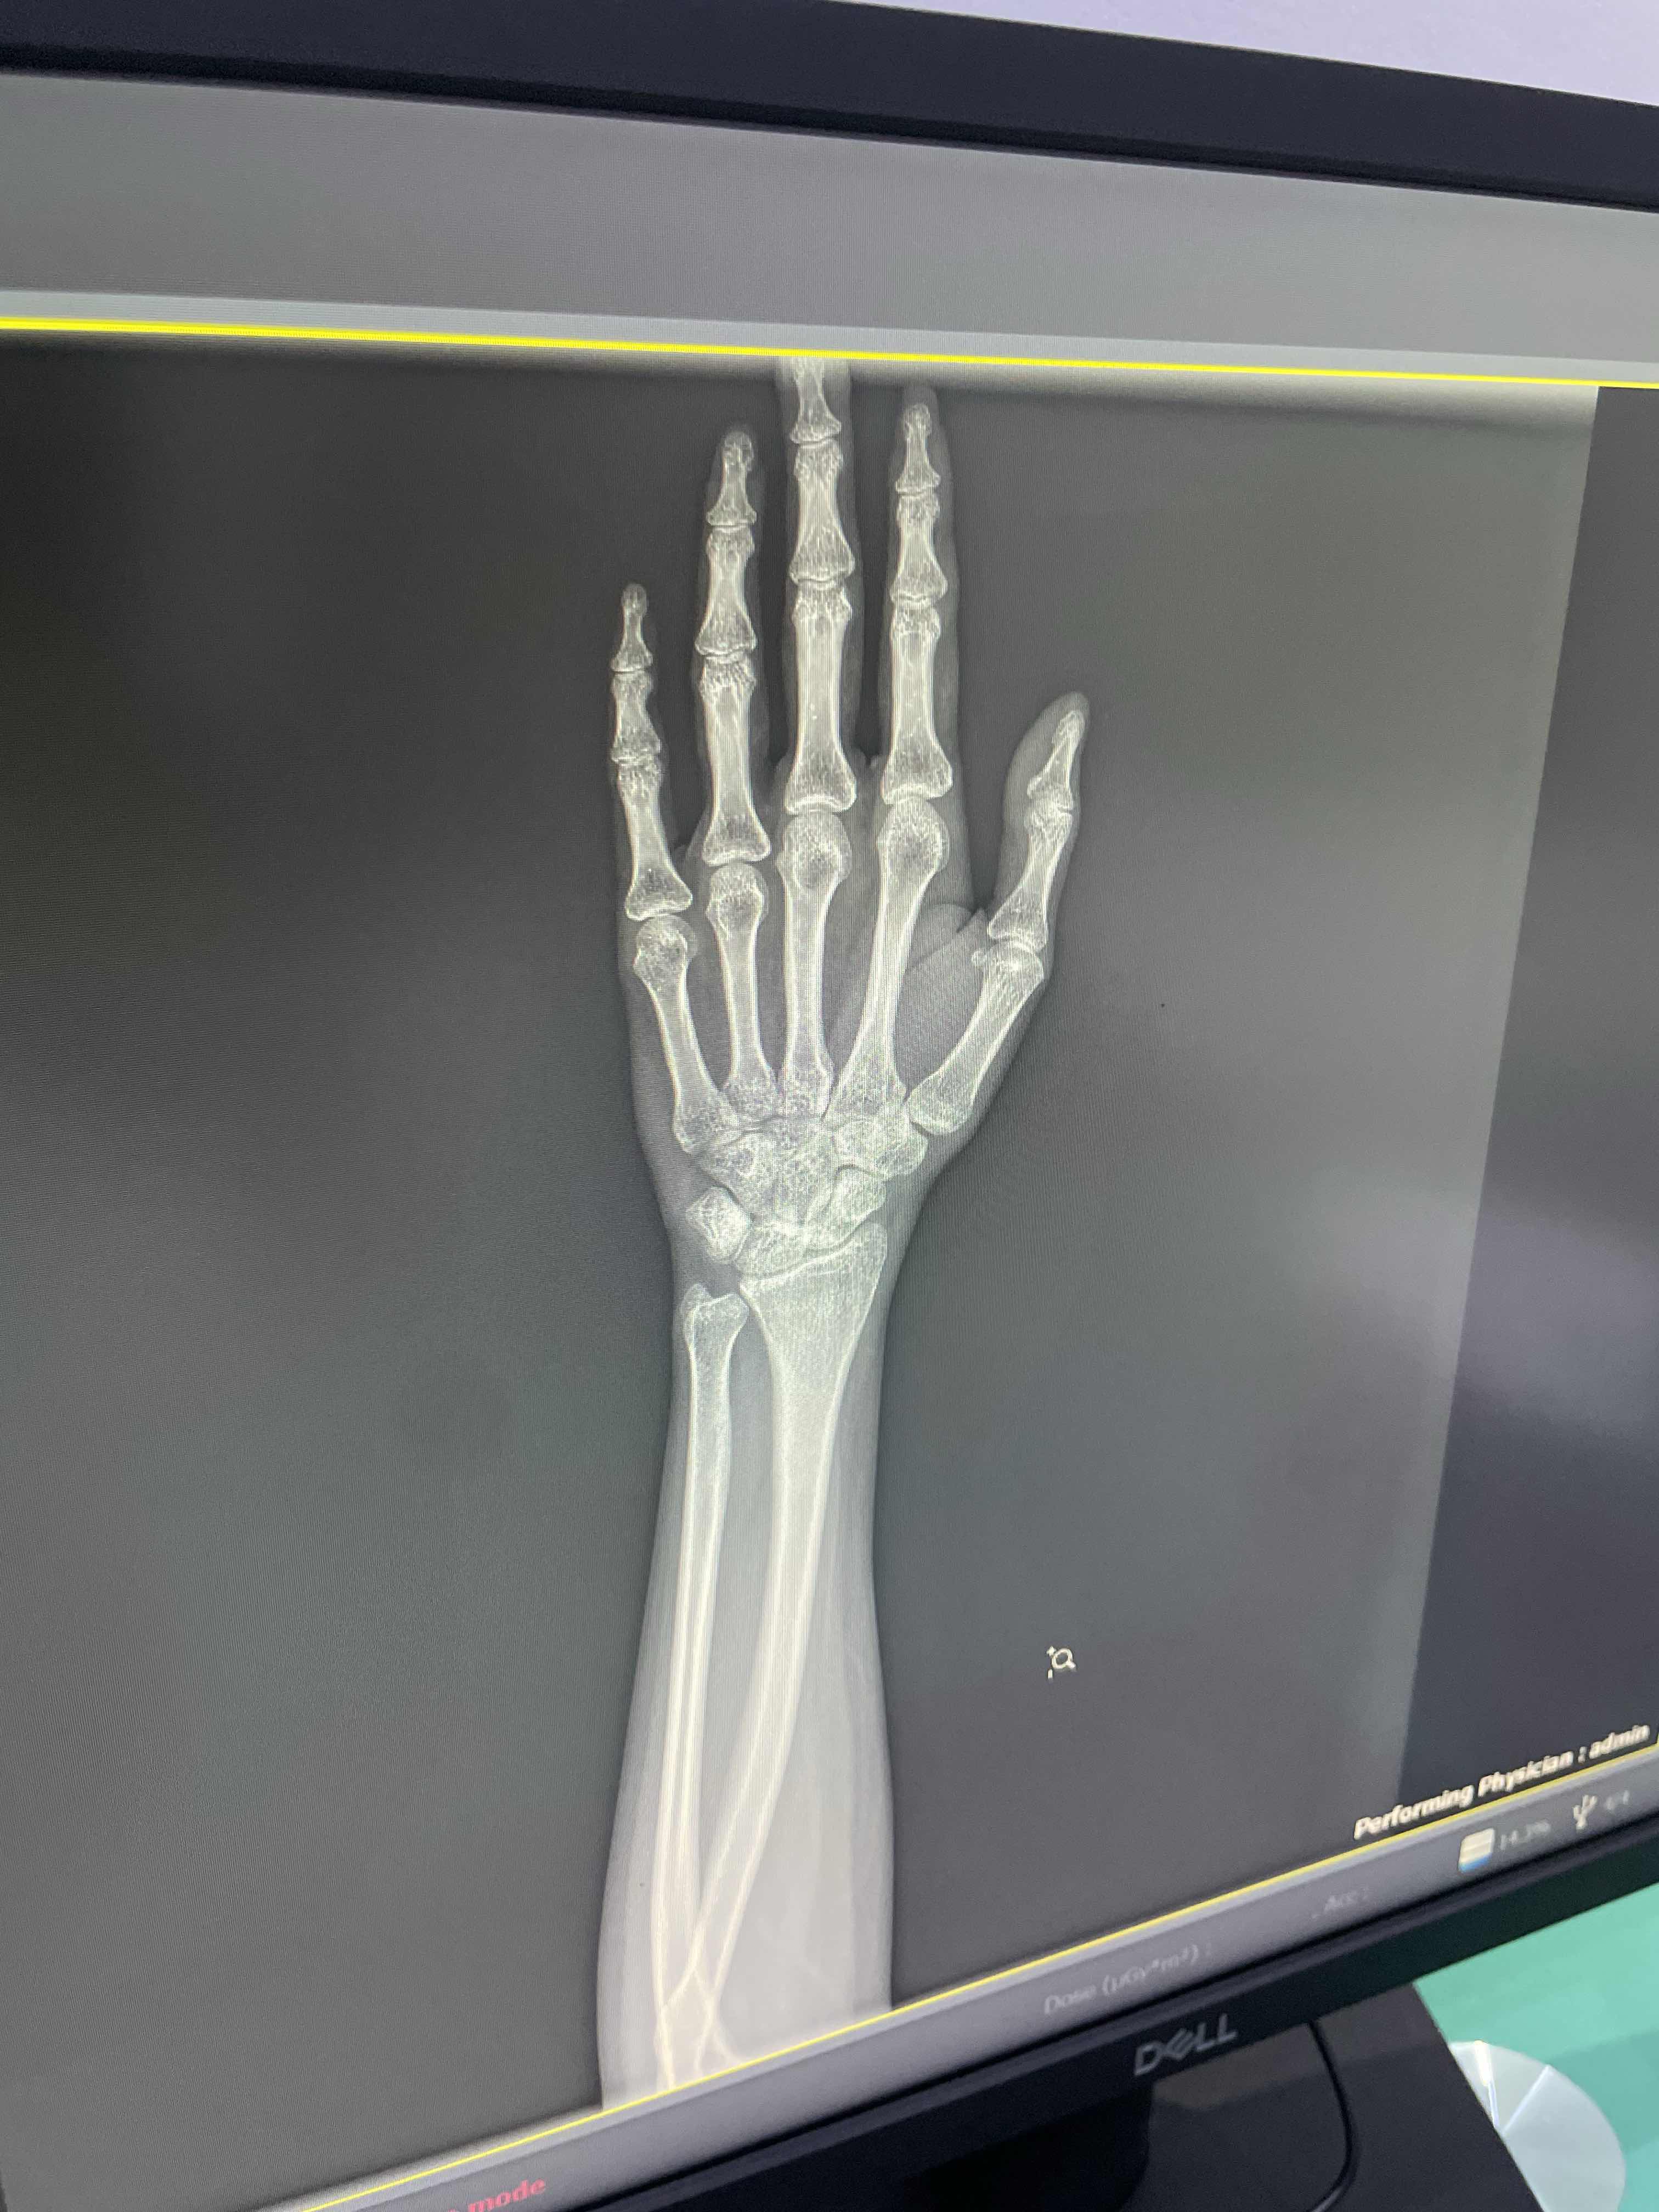

هل يوجد كسر وتمزق باوتار اليد

هل يوجد كسر وتمزق باوتار اليد ١٢ يوم من يوم الطيحه ٩ ايام من يوم ركبت الجبس الاعراض قبل اركب الجبس ورم ب المفصل ولون المفصل ازرق بس ما في الم فيه الا اذا لفيت يدي او شديت عليها